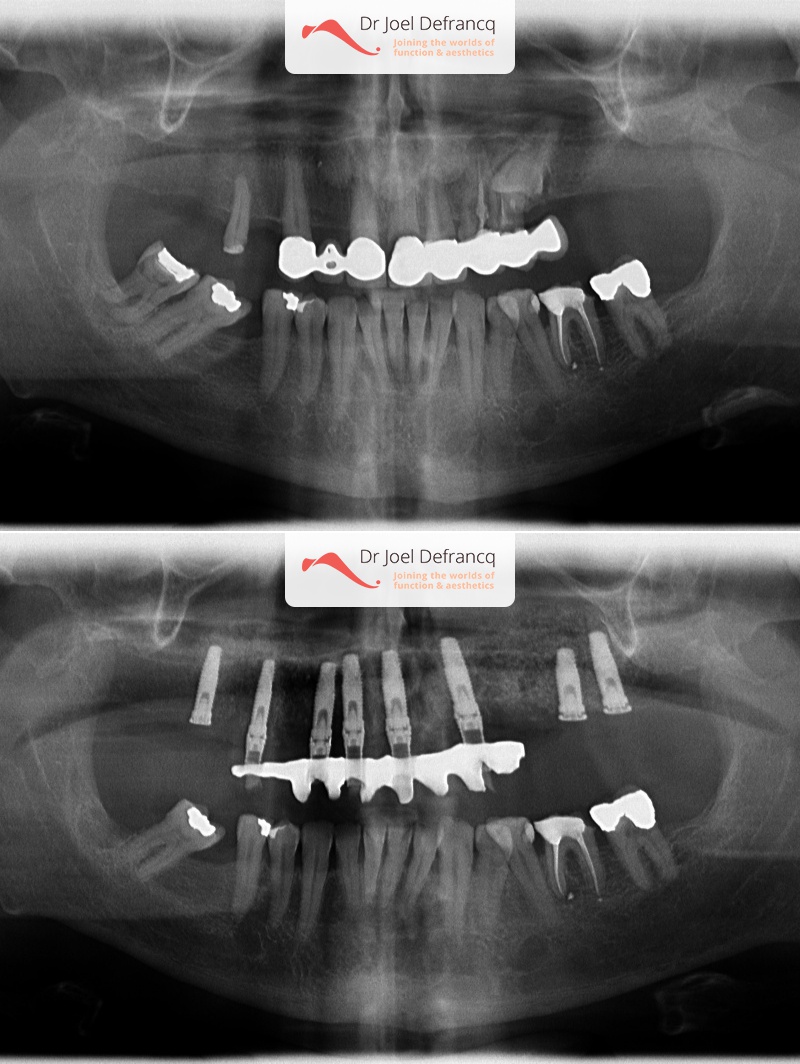

Dentale diagnose

- Klasse I

Behandeling tandheelkundige implantaten

- Vaste tanden op implantaten (bovenkaak)